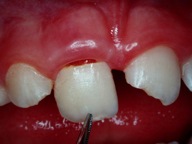

Bei der Therapie von Zahnfrakturen stehen aus endodontischer Sicht vitalerhaltende Maßnahmen im Vordergrund. Zähne mit nicht abgeschlossenem Wurzelwachstum können so ihr Wurzellängen und –dickenwachstum fortsetzen. Aus restaurativer Sicht gilt es Funktion und Ästhetik möglichst optimal wiederherzustellen. Die restaurative Versorgung von Kronen- Wurzel-Frakturen ist durch die subgingival liegenden Defektgrenzen massiv erschwert. Zur Defektdarstellung und Herstellung der biologischen Breite bieten sich verschiedene Alternativen an. In vielen Fällen ist eine kieferorthopädische oder chirurgische Extrusion ein sinnvoller Weg im Sinne der Zahnerhaltung.